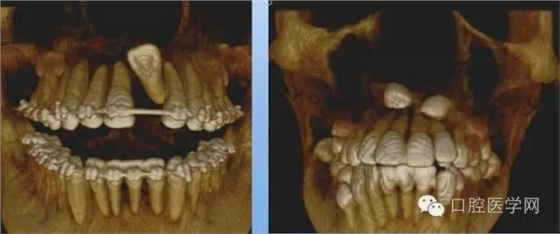

3.牙齒數(shù)目異常

額外牙

X線表現(xiàn):最多見(jiàn)于上頜兩中切牙之間;圓錐形,根短小;拍攝X線片可確定額外牙的數(shù)目、位置、形態(tài)與鄰牙的關(guān)系。